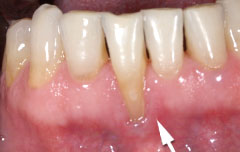

| 深い虫歯のケースでは、切除療法を行い虫歯を取り除き、健全な歯質を歯肉の上に出し、歯肉の盛り上がりを数ヶ月待ってから歯型をとります。 |

||

| 一見分りませんが、かなり歯周病が進行していました。歯周ポケットの改善や歯槽骨を平坦にして清掃しやすい環境を整えます。数ヶ月、歯肉の盛り上がりを待ってから適合の良いクラウンを被せます。 | ||